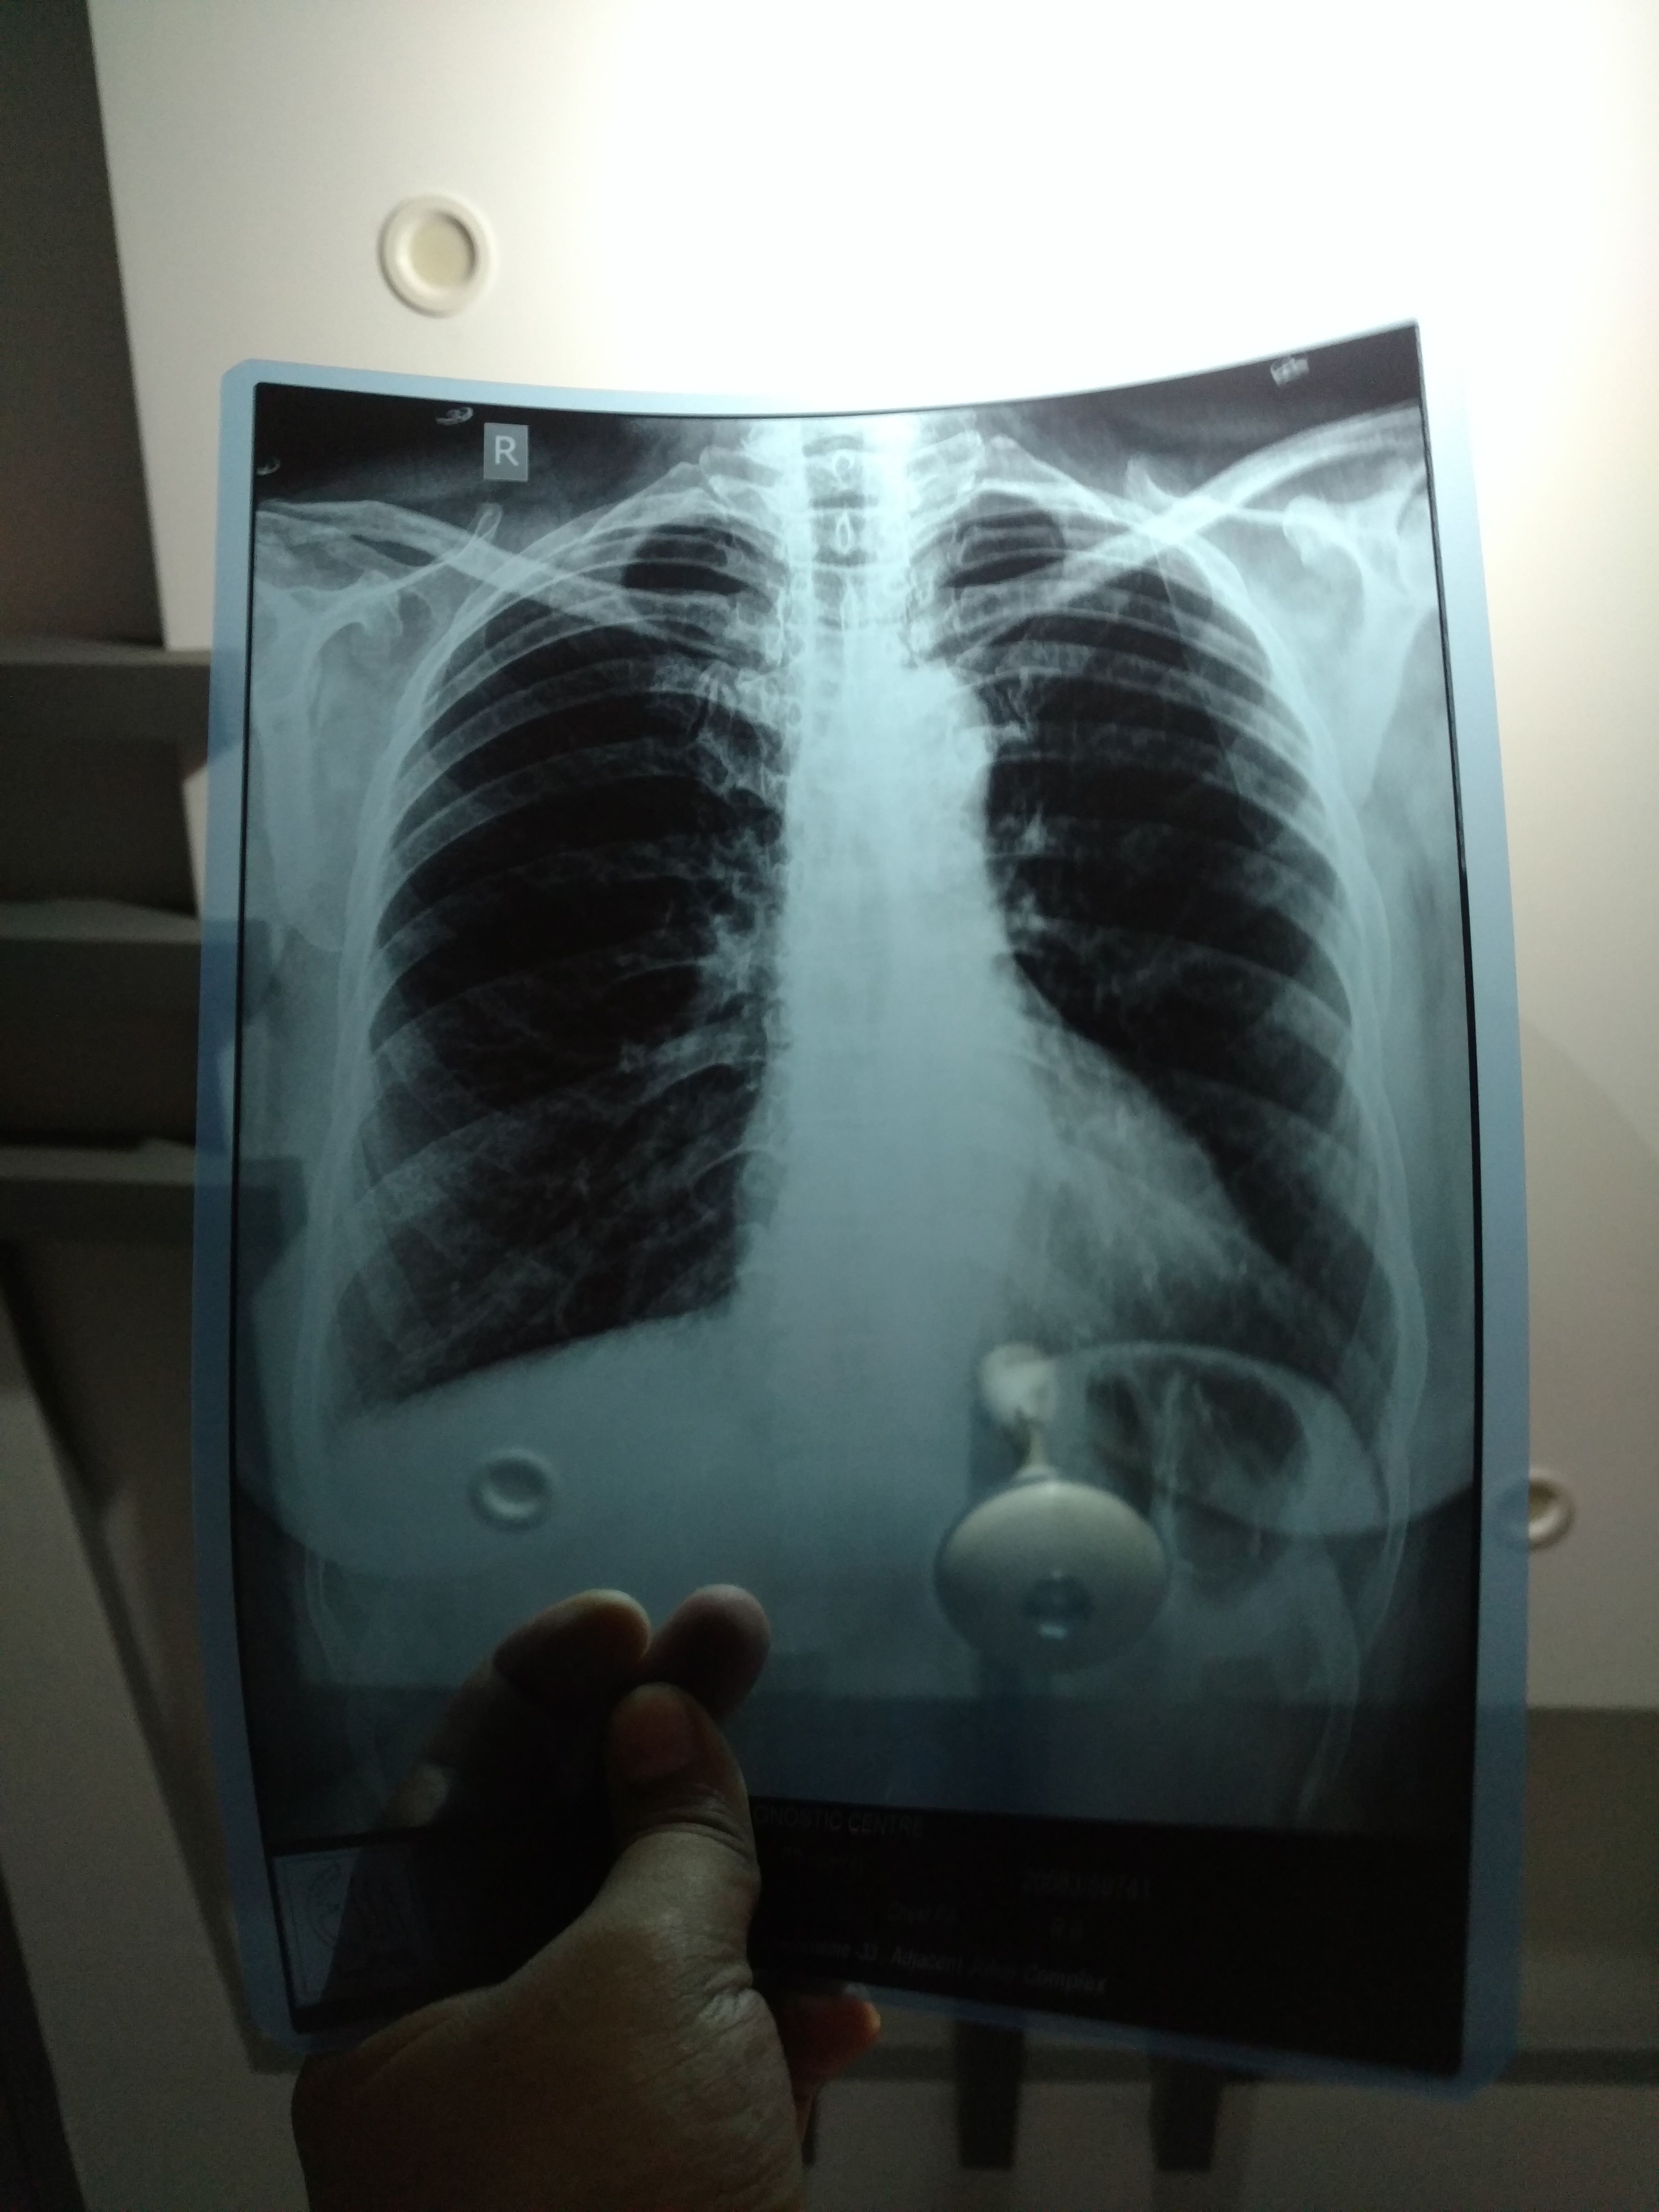

Kindly do chest xray and then let me know..

It's normal sir

X-ray Report

But can u show me the xray film

Because reporting chest xray is our job and most of the people don't know it

I have uploaded sir

Where u have uploaded I can't see?

FYI

Chest xray Is not normal.. It's hyperinflation... U must do a PFTS test...